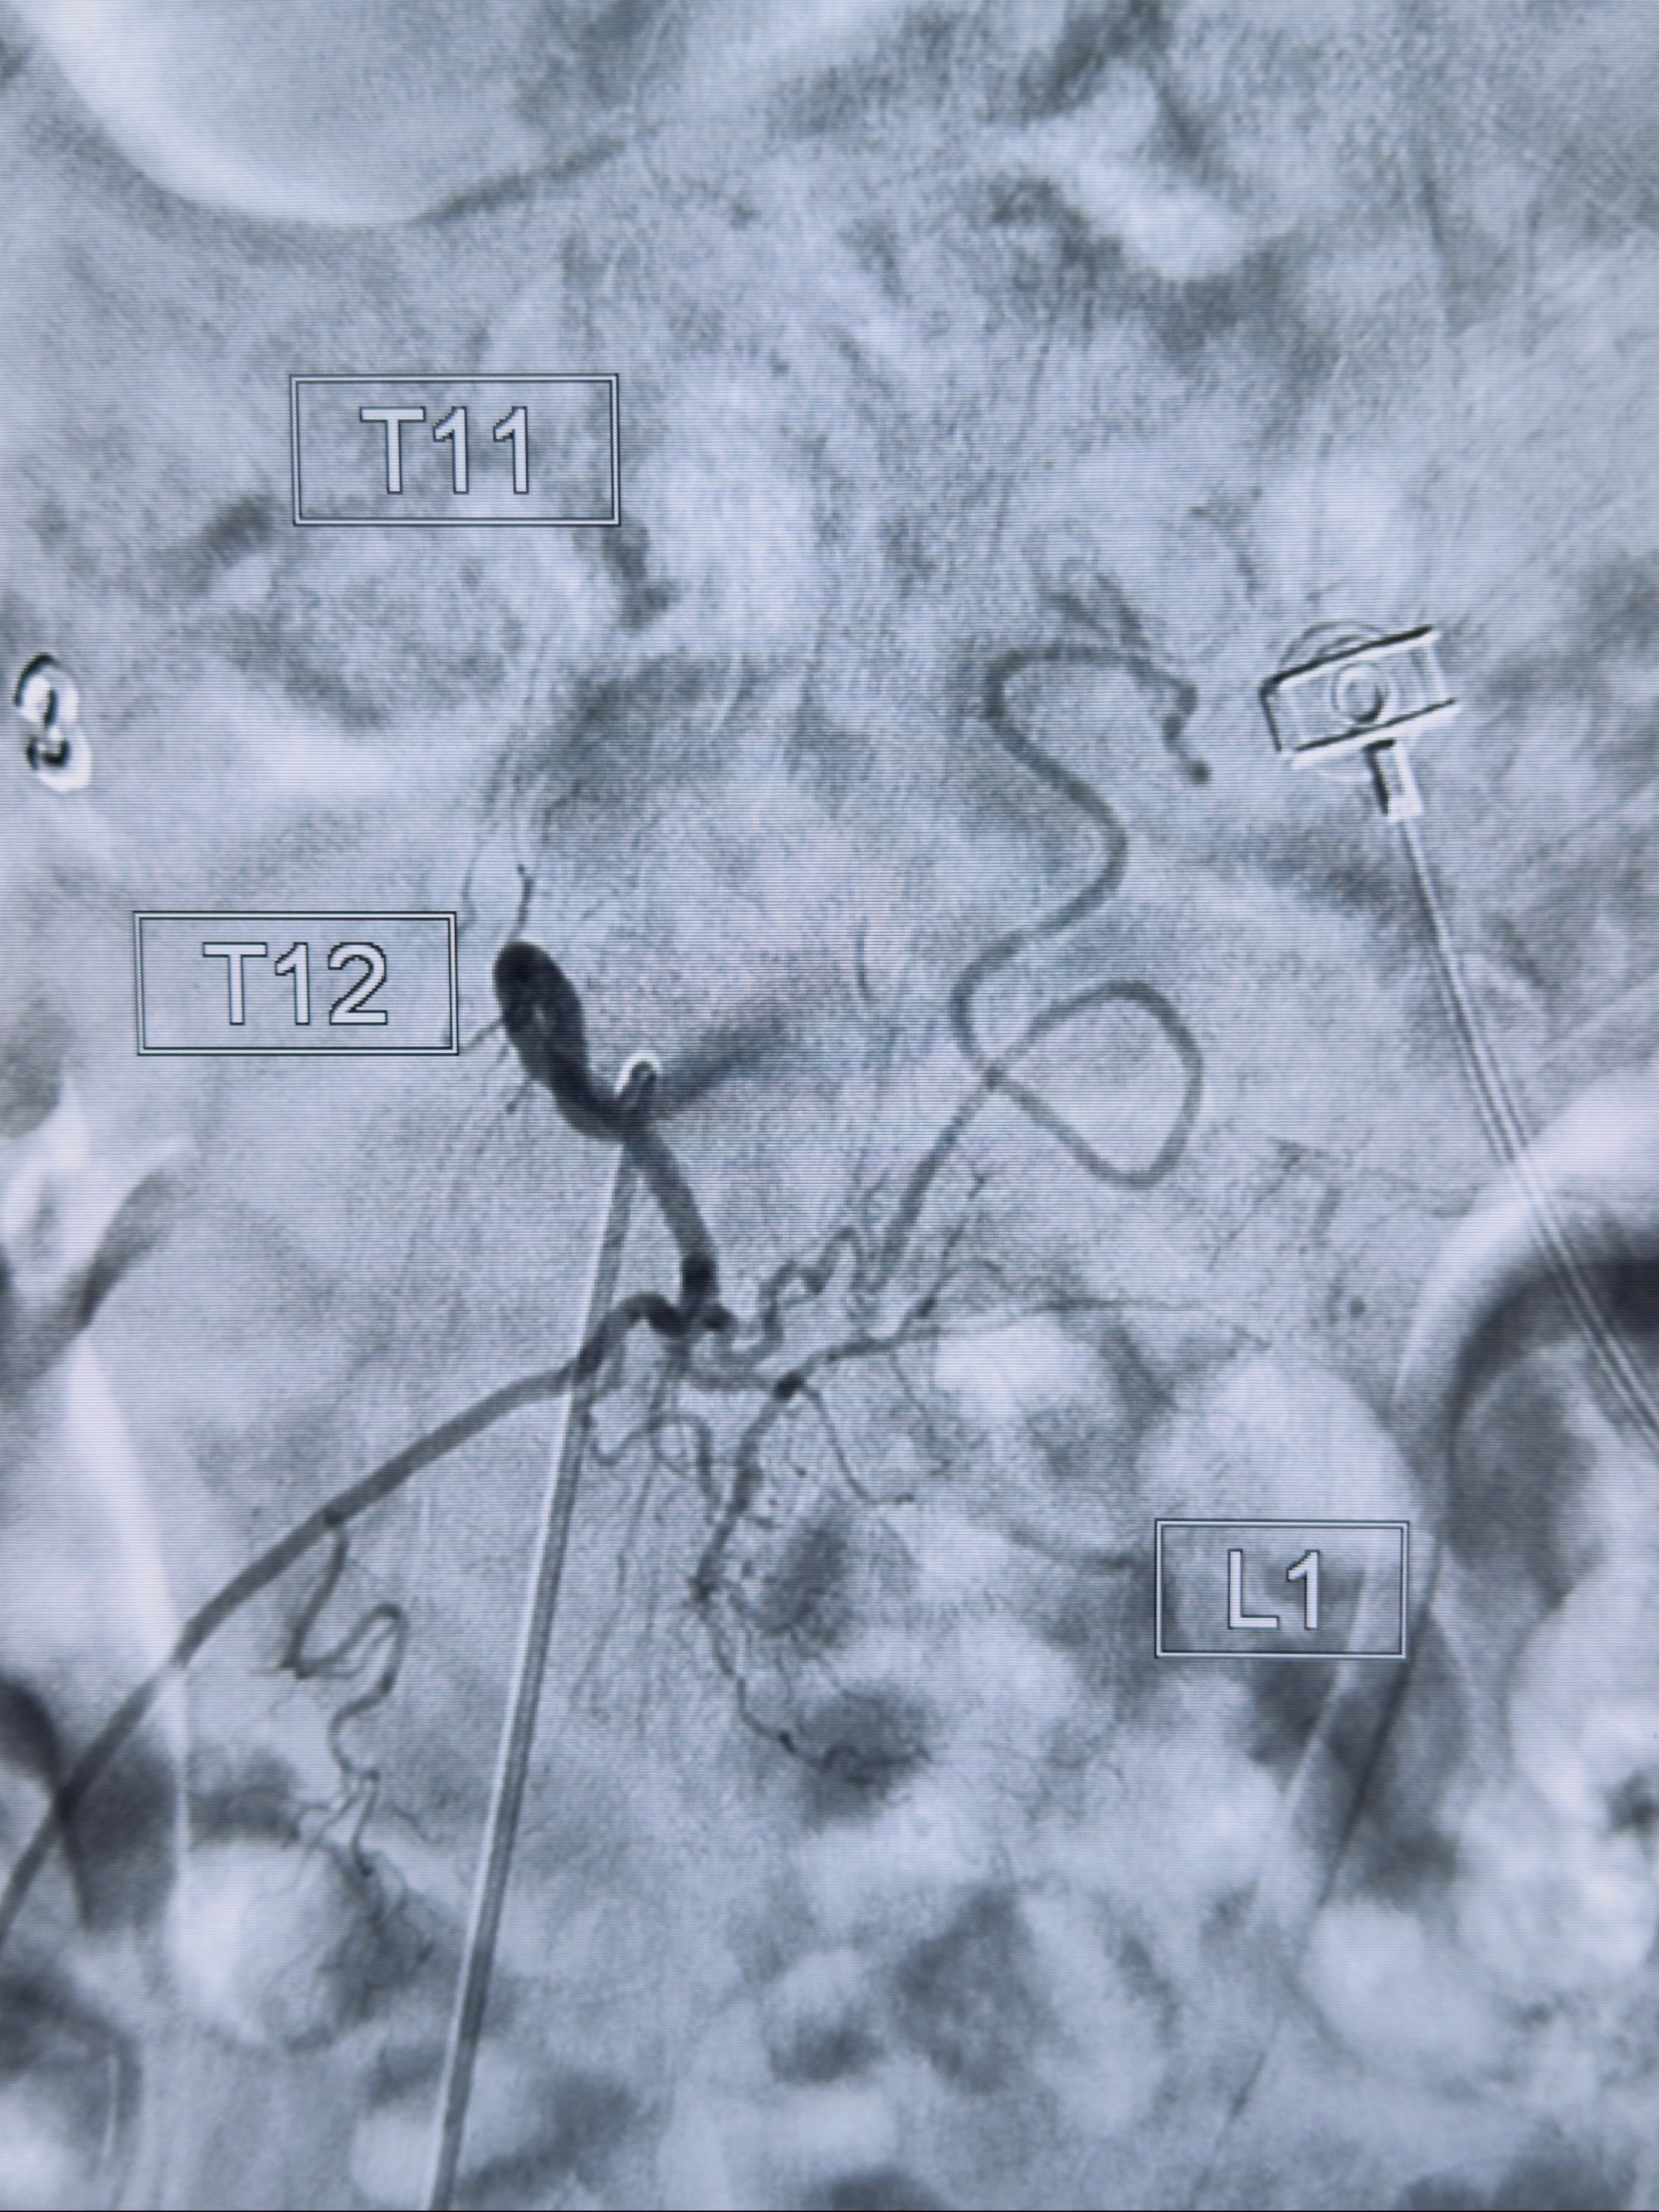

2023-10-13DSA:右侧L1水平硬脊膜动静脉瘘,供血动脉为右侧L1,附近动脉未见明确吻合供血,供血动脉处可见脊髓前动脉发出